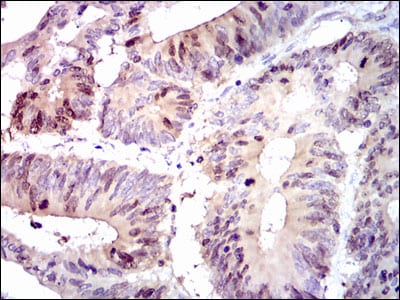

Immunohistochemical analysis of paraffin-embedded human ovarian cancer tissues using PBK mouse mAb with DAB staining.

Figure5: Immunohistochemical analysis of paraffin-embedded human colon cancer tissues using PBK mouse mAb with DAB staining.